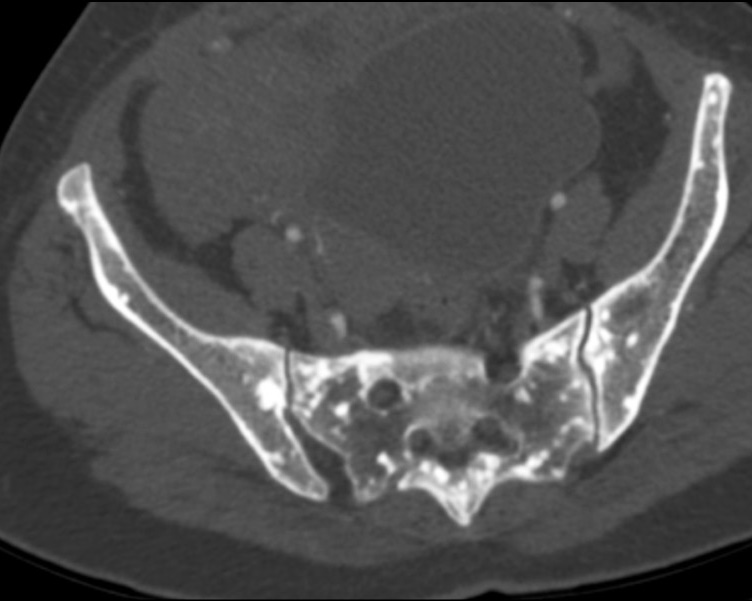

Osteopoikilosis in the ribs, pelvic region and spine: a case report

Abstract

Osteopoikilosis is a rare inherited benign bone dysplasia incidentally found on radiological exams. It is characterized by a specific radiological pattern: diffuse, round or oval, symmetrically shaped sclerotic bone areas distributed throughout the skeleton. It is essential to do a correct diagnosis because these lesions could be easily confused with bone metastasis.

We reported a case of an osteopoikilosis patient presenting to our clinic with transient loss of consciousness and without any numbness, tingling and weakness in the legs or other parts of the body. The computed tomography scan showed multiple small sclerotic foci bone islands, scattered throughout the thoracic and lumbar spine, ribs, pelvic bone, sacrum and bilateral proximal femur. No significant increase in the activity was detected in technetium-99m whole-body bone scintigraphy. The patient was diagnosed with characteristic radiological findings of osteopoikilosis and was followed up.

481-487